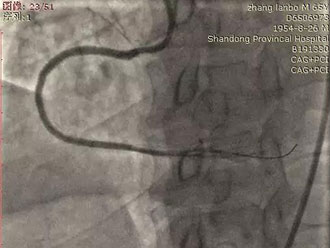

图四:Stingray球囊辅助下重回真腔